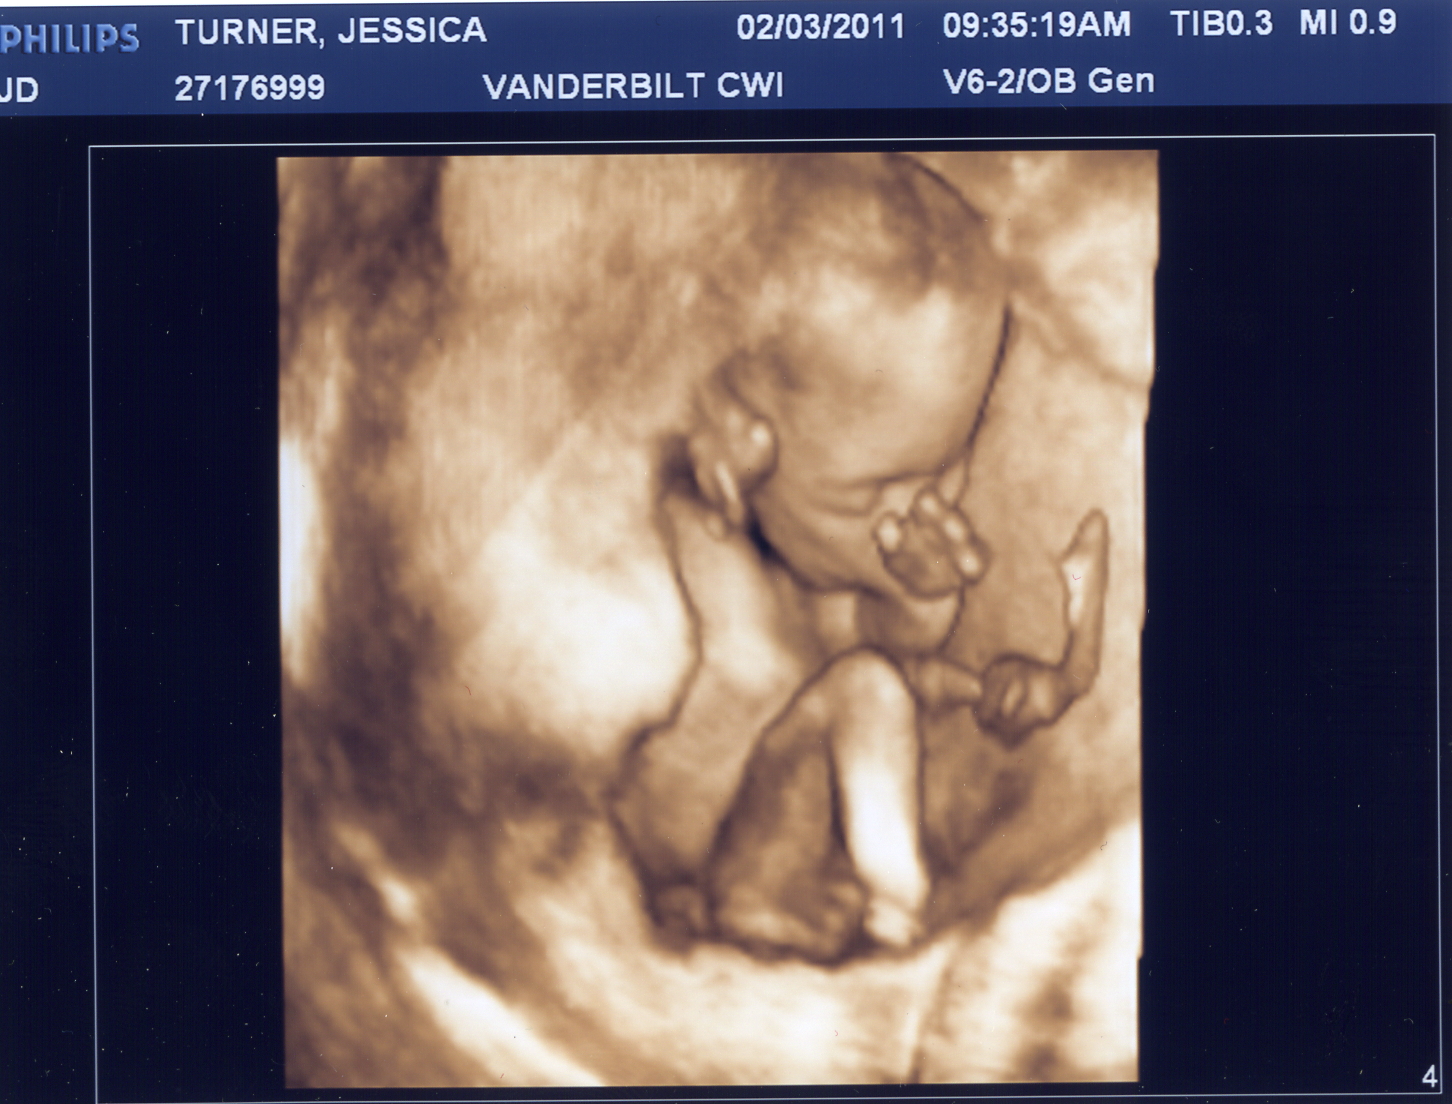

We are thrilled to introduce Miss Adelyne Turner. (Middle name TBD).

She is healthy, very active and quite the thumb-sucker, as you can see below.